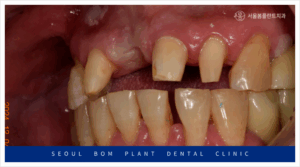

오늘은 위턱 앞니의 임플란트 탈락으로

송파구치과 서울봄플란트치과를

내원해 주신 사례를

소개해 드리겠습니다.

환자분께서는 50대 초반의

남성분으로 타 치과에서 했던

오른쪽 위턱 첫 번째 앞니(#11)의

임플란트가 빠져 상담을 위해

내원해 주셨는데요.

앞니는 원래도 잇몸뼈가 얇은 데다가

환자분께서는 임플란트 주위염으로 인해

잔존 잇몸뼈가 약해져

기존 임플란트가 탈락한 상황이었는데요.